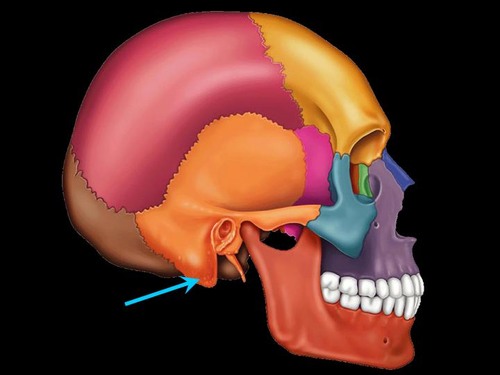

sphenoid bone (lateral view)

temporal bone

maxilla (lateral view)

zygomatic bone (lateral)

styloid process

external auditory meatus

mastoid process